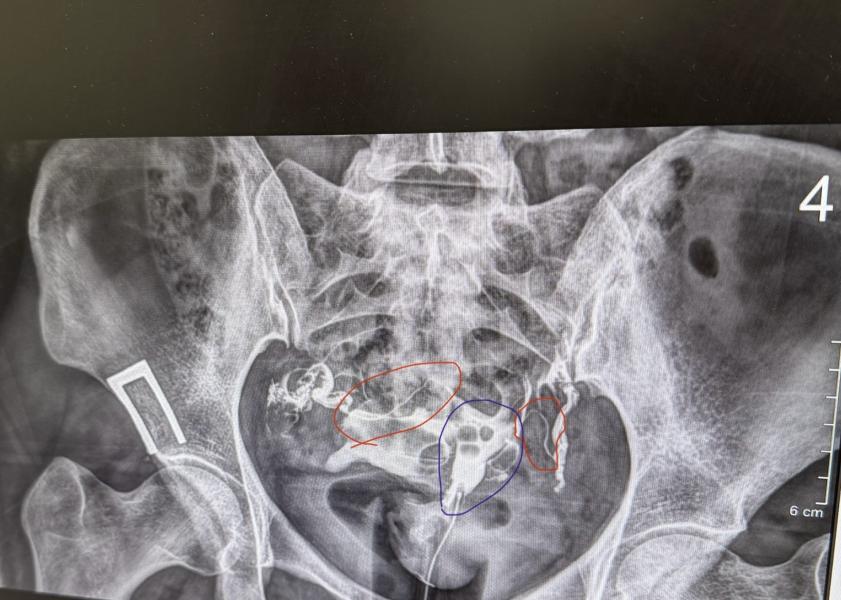

Сделала сегодня ГСГ маточных труб. Трубы проходимы, ни каких патологий нет. Три года назад на лапароскопии были с признаками хр.воспаления, где то расширены и извитые. Прикладываю рентген с контрастом. Может кто понимает, где там трубы? Я обвела красным по моему мнению трубы, синим матка 🤭